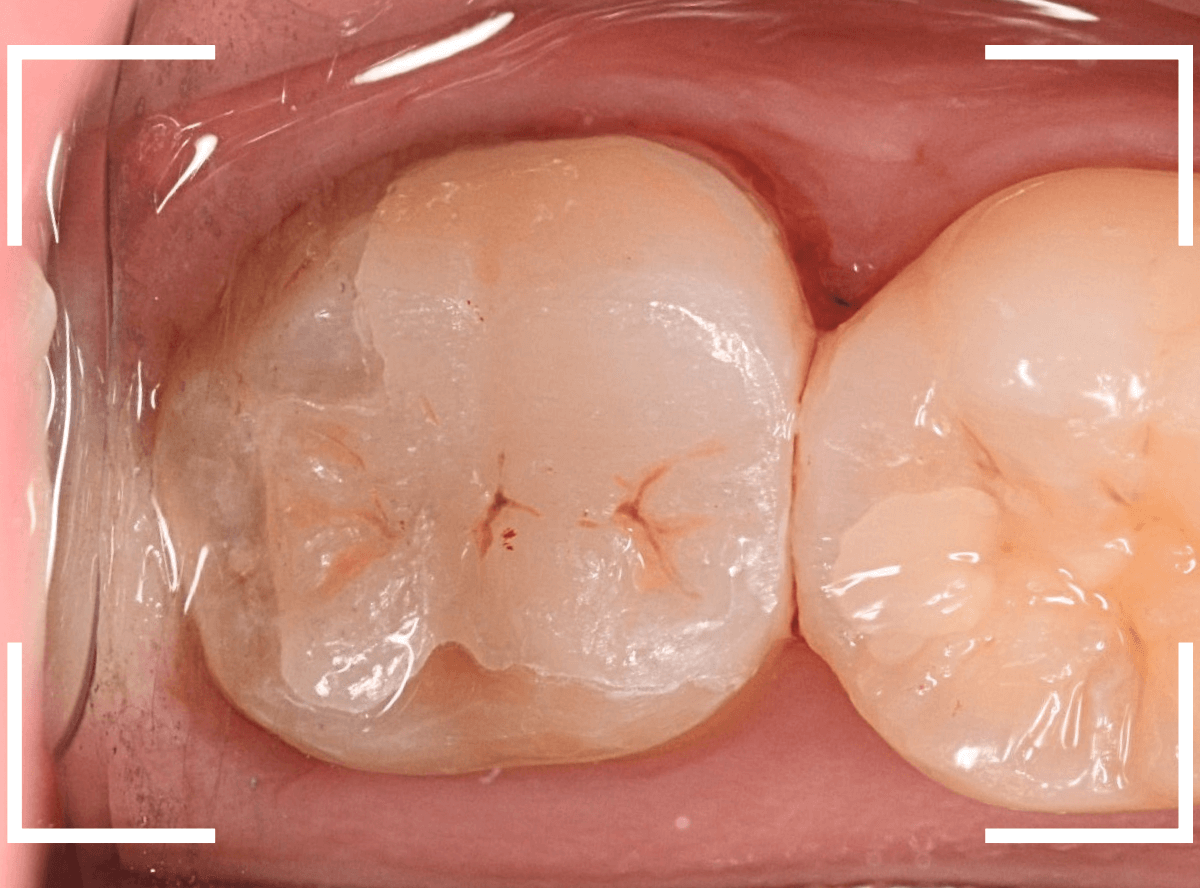

治療再開後、セラミックの最終修復を希望されましたので、歯をトリミングし、型取りします。

模型上で精密に製作します。

治療後の状態です。

治療後の定期メンテナンスに来院されない患者さんもまれにいらっしゃいますが、一定期間来院のない方は破折などの際の保証も受けられません。

くれぐれも忘れずに来院していただくようにお話しし、終了となりました。

| 治療回数 | 3回 |

| 治療期間 | 3週間(中断期間は除く) |

| 費用 | ジルコニア・インレー (70,000円) +保険治療費用(虫歯除去など) |